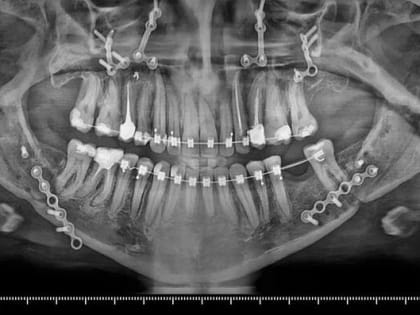

Волгоградские медики провели сложную операцию по исправлению прикуса

Пациентке требовалось комбинированное лечение Врачи городской клинической больницы №1 провели серию сложных операций пациентке с гнатической формой зубочелюстной аномалии.

Волгоградские хирурги вылечили пациентку с аномалией прикуса

Фото предоставлено комитетом здравоохранения Волгоградской области Волгоградские челюстно-лицевые хирурги Роман Стасюк и Анастасия Мулина прооперировали пациентку с зубочелюстной аномалией.